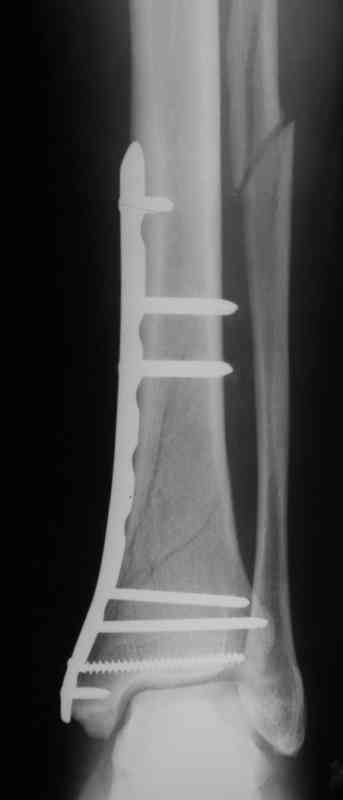

Выполнил MIPO предизогнутой метафизарной LCP

И все же немного критики:1) Вы добивались анатомичной репозиции, которая требует абсолютной стабильности, которая в свою очередь возможноа только в условиях межфрагментарной компрессии. Пластина уложена как мостовидная, не хватает стягивающнго винта. 2) есть укорочение малоберцовой кости, необхордимо восстановить ее длину! В таком виде я бы не стал разрешать раннюю нагрузку. Добавить самую малость: стягивающий винт и остеосинтез малоберцовой кости и больной может наступать сразу.

В этом случае остеосинтез выполнялся малоинвазивно и я не добивался абсолютной стабильности преднамеренно. Стабильность относительная и ст. её зависит от механических свойств импланта;возможно, нужно было взять длиннее пластину, увеличив её рабочую длину

Все справедливо для оскольчатого перелома, когда вы не добиваетесь анатомичной репозиции. При простом переломе адекватной будет анатомичная репозиция, и она у Вас получилась закрыто. Если Вы изначально предполагали относительную стабильность, то штифт позволил бы более раннюю и агрессивную реабилитацию